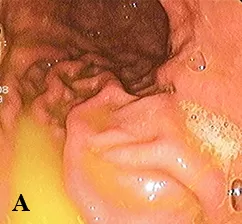

Диагностика ДГР при ЭГДС легко устанавливается по наличию желтого, зеленого окрашивания содержимого желудка, т. е. по наличию желчи в желудочном соке. Желтое содержимое желудка соответствует легкой степени (см. рис. 1а); прозрачное светло-зеленое — средней степени (см. рис. 1б) и мутное темно-зеленое — тяжелой степени рефлюкса (см. рис. 1в). ЭГДС не может провоцировать ДГР, так как интубация пищевода и прохождение эндоскопа по пищеводу занимает несколько секунд. Факт поступления желчи из привратника не является физиологическим и не может быть классифицирован как истинный ДГР.

Рис. 1. Степени тяжести ДГР при ЭГДС.